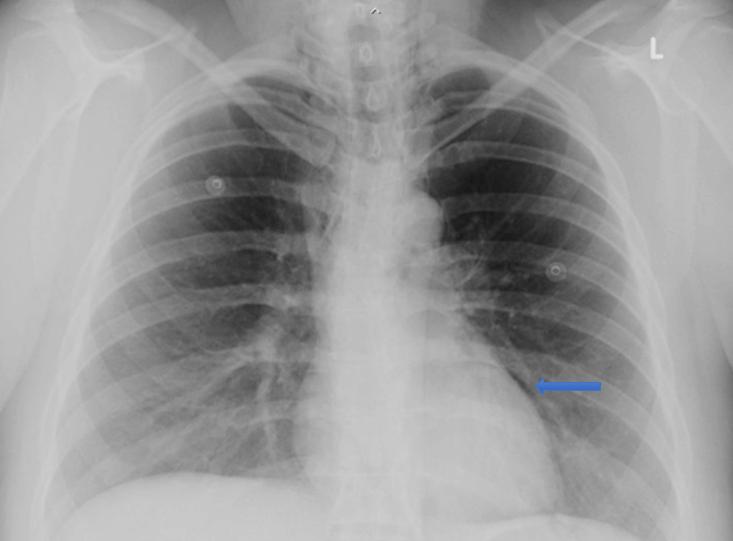

Six hours postpartum she complained of chest pain associated with mild dyspnoea and altered voice. Her vital signs were unremarkable and stable. She was examined by the on-call GP/obstetric physician who noted subcutaneous emphysema of the neck and chest on palpation. Her chest was clear with normal breath sounds on both lung fields. The physician also recognised crunching and crackling sound heard over the precordium, synchronous with the heartbeat (Hamman’s sign). A chest radiograph revealed evidence of pneumomediastinum (Fig1). After consulting with the respiratory team at the tertiary referral hospital, she was managed with analgesia, supplemental oxygen and close observation at the community hospital. A repeat chest X-ray 24 hours later showed resolution of the pneumomediastinum, and the patient’s symptoms improved. The subcutaneous emphysema resolved spontaneously after 3 days and she was discharged home. She was followed up by the respiratory team 2 months later with no further complications.

Figure 1: Chest X-ray of the patient, showing pneumomediastinum.